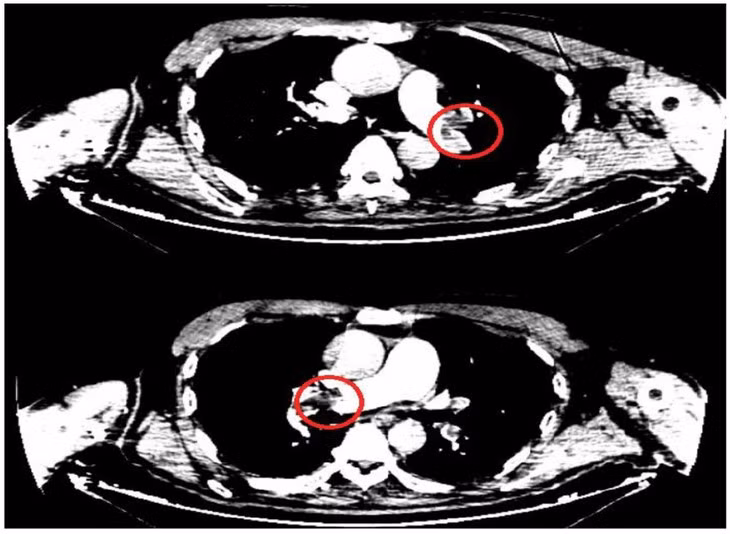

Nghi ngờ tình trạng thuyên tắc phổi cấp, bệnh nhân được chụp cắt lớp vi tính chẩn đoán huyết khối động mạch phổi hai bên và lập tức chuyển Bệnh viện Đa khoa tỉnh Quảng Ninh.

![]() |

| Hình ảnh huyết khối động mạch phổi cả 2 bên của bệnh nhân. - Ảnh BVCC |

Hai trường hợp chúng tôi điều trị vừa qua xảy ra rất đột ngột, nặng nề với tình trạng huyết khối mạch phổi một hoặc hai bên trên nền bệnh nhân có yếu tố nguy cơ. Các trường hợp này đều được nơi điều trị ban đầu phát hiện sớm, chính xác và chuyển khoa Hồi sức tích cực điều trị tiêu sợi huyết kịp thời, vì vậy người bệnh hồi phục tốt, di chứng tối thiểu.